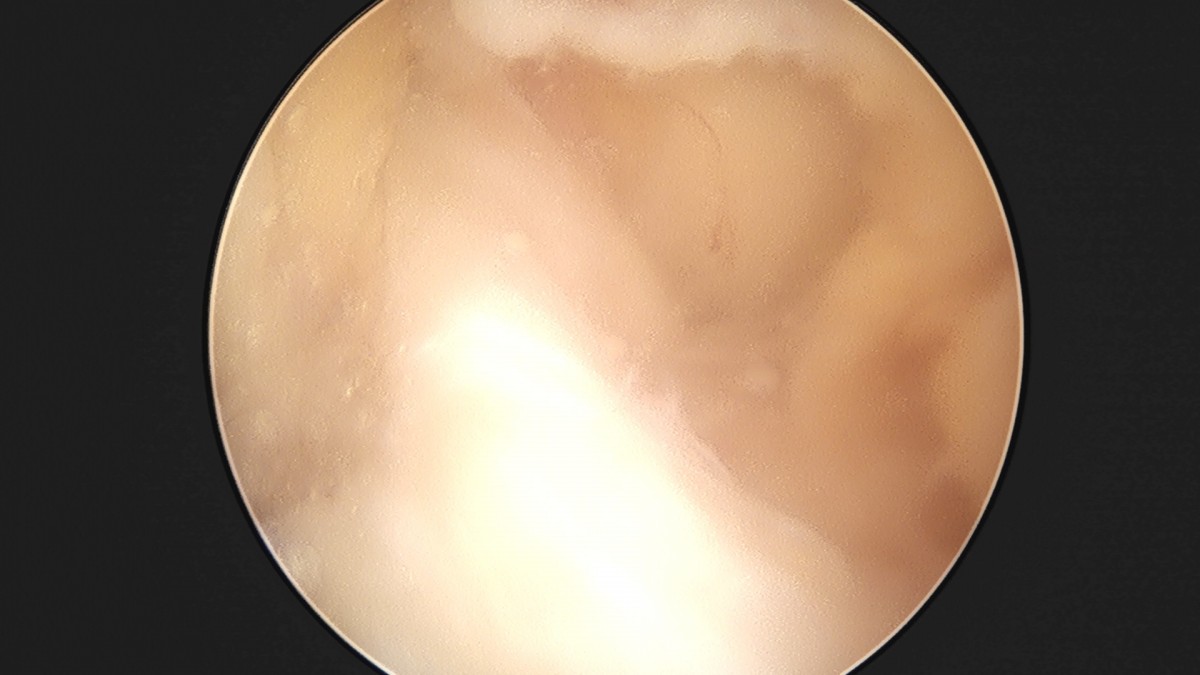

이재상원장님 무릎 반월상 연골판 절제술 조미O 환자

dae765e4d9ac96aee867c9d6292d8784_1758005941_8534.jpg